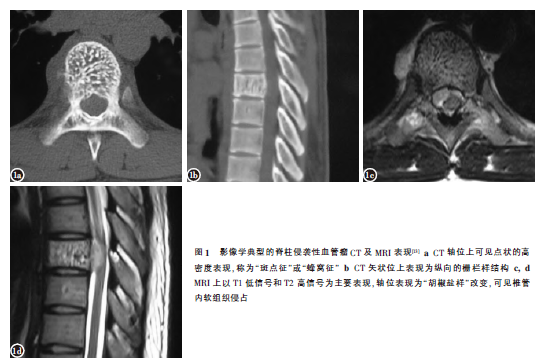

影像学诊断 根据影像学特征,Gaudino等将脊柱血管瘤分为三类:典型脊柱血管瘤、不典型脊柱血管瘤、脊柱侵袭性血管瘤,其中脊柱侵袭性血管瘤多有典型的影像学表现,包括栅栏样改变、蜂窝征及斑点征等,但部分脊柱侵袭性血管瘤无上述典型表现。Wang等进一步将侵袭性血管瘤分为典型(图1)和不典型两类。不典型的特点包括膨胀性或溶骨性骨质破坏、椎体压缩骨折

、多节段受累及、椎管内成骨性压迫、MRI信号不典型、病灶中心位于附件等。影像学不典型的侵袭性血管瘤易引起误诊,文献报道可误诊为浆细胞